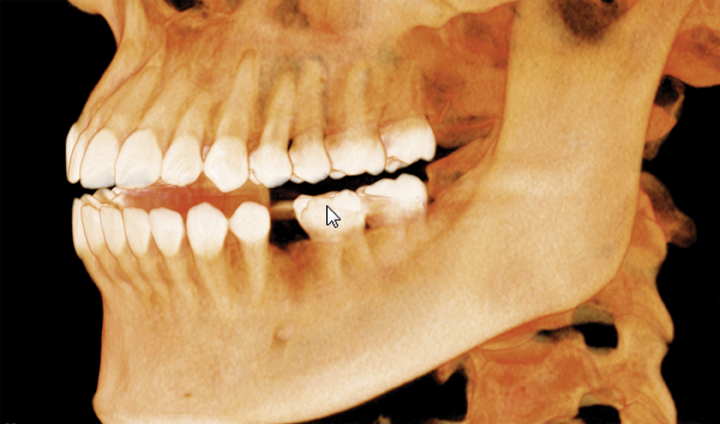

When a member of my front office staff, Yari, confided in me that she had a toothache, I took a bitewing radiograph (DEXIS™ Platinum) and discovered that she had deep distal decay on tooth #20. Intraoral examination revealed a fracture beyond the cervical extent of the tooth (Fig. 1). The tooth was non-restorable, so she was facing extraction and had several choices about how to replace that tooth. We discussed the possibility of a removable partial denture, a fixed bridge, or an implant.

Fig. 1 Fig. 2